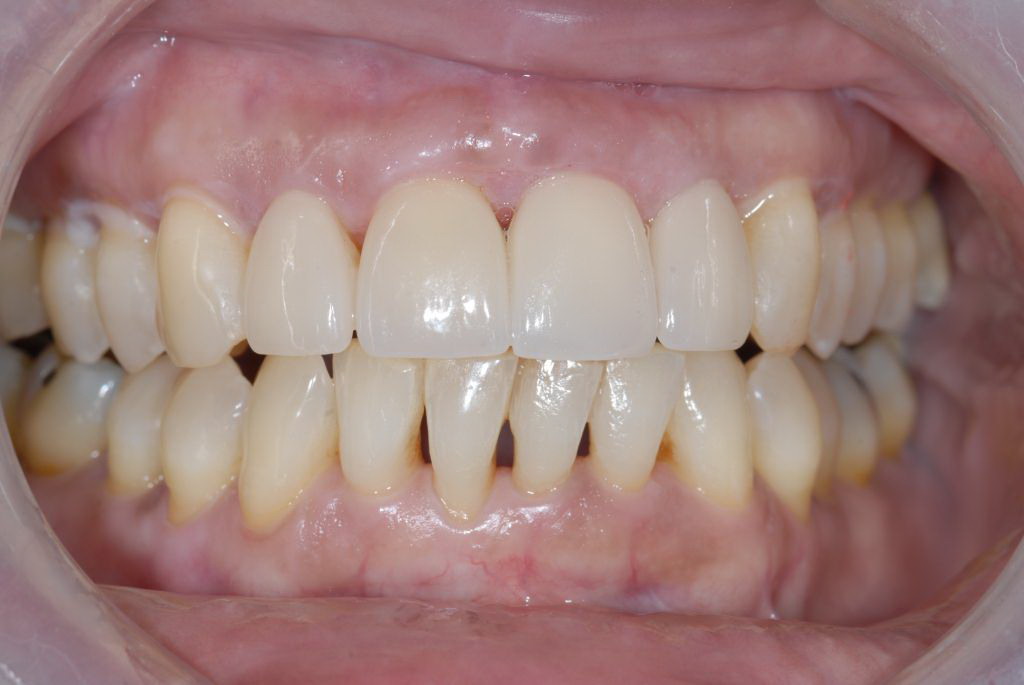

A patient in her 60s wanted to improve her smile but declined orthodontic treatment in favor of porcelain veneers (Figure 13). However, addressing her 8-mm pocket was the first step. The practitioner created biologically clean root surfaces using ultrasonic open-flap debridement, finishing burs, and manual tool instrumentation. Next, a mineralized freeze-dried bone allograft saturated in platelet-derived growth factor (Figure 14) using chemotaxis pulled the stem cells capable of regeneration into the site where repopulation was needed. Prior to closure, a resorbable membrane, polylactic acid-guided tissue regeneration—known for periodontal regeneration—was used (Figure 15). At 10 weeks, adequate healing had occurred. The patient at 6 and 10 weeks showed continued healing. Although some postoperative recession was evident, probing depths were less than 2 mm, and the patient was referred back to the restorative dentist for restorative therapy. As of this writing, she has not lost any teeth and is periodontally stable (Figure 16).

The pretreatment situation.

Figure 1

Figure 13

The final restorative situation. (Restorative therapy by Dr. B. Wilk, Chalfont, PA.)

Figure 16